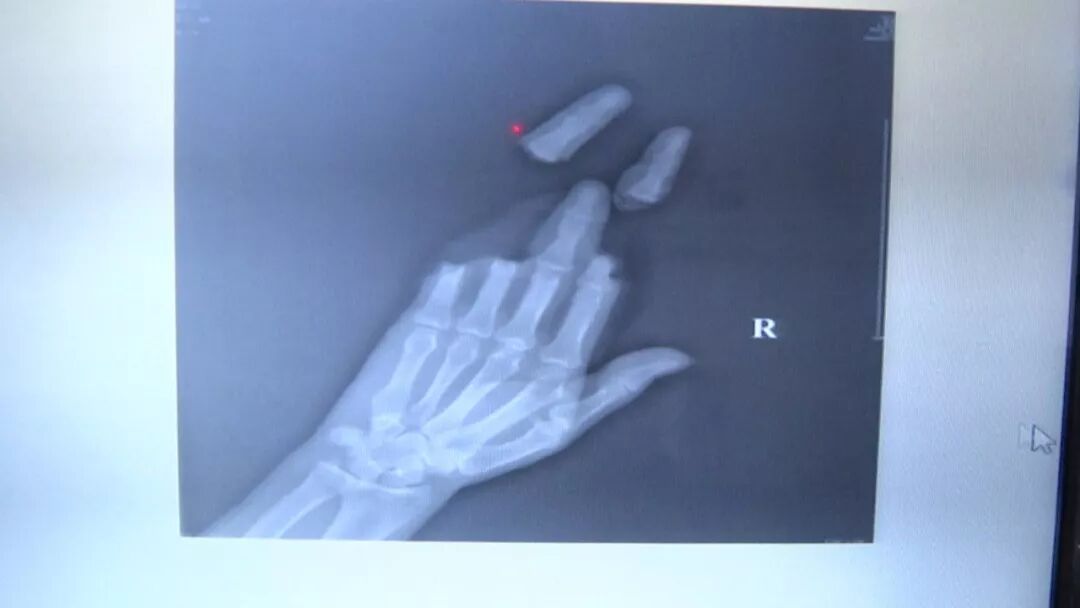

受伤男子说,风筝线大约2毫米直径,遇到狂风勒在手上时,就像一把利刃。他四根手指离断,另外一名同伴半个手掌离断,两人伤口处血流不止。事发后被120送至南通中山骨科医院急救。

南通中山骨科医院手足显微外科主任 金德镐:(其中一个)患者当时来的时候,第二个到第五个手指都是离断的,虽然第三根手指连着,但是只是连着骨头,所有的血管神经、肌腱都是离断的。

断指再接的黄金时间在六个小时内,手术越快进行越好。医院开辟绿色通道,迅速将两名男子推进手术室。从昨天下午三点,到今天早晨7点,经过16个小时的努力,终于将两名患者离断的手指、手掌全部接上。